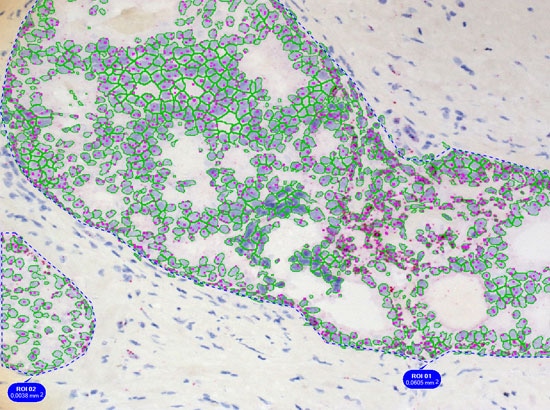

The nuclear segmentation algorithm is highly efficient in difficult situations in tissue and can be set with two values only - mean nuclear size and nuclear channel background threhshold. The cell compartment algorithm provides a large amount of flexibility with a few simple settings (see below, yellow=segmented nuclei, blue nuclei positive for DAB or cytoplasm positive for Permanent Red marker).

Simple context based analysis can easily be done in HistoQuest by using manual region tools. Drawing the regions takes a negligible amount of time and provides data for epithelial areas and stroma separatelyin this example.